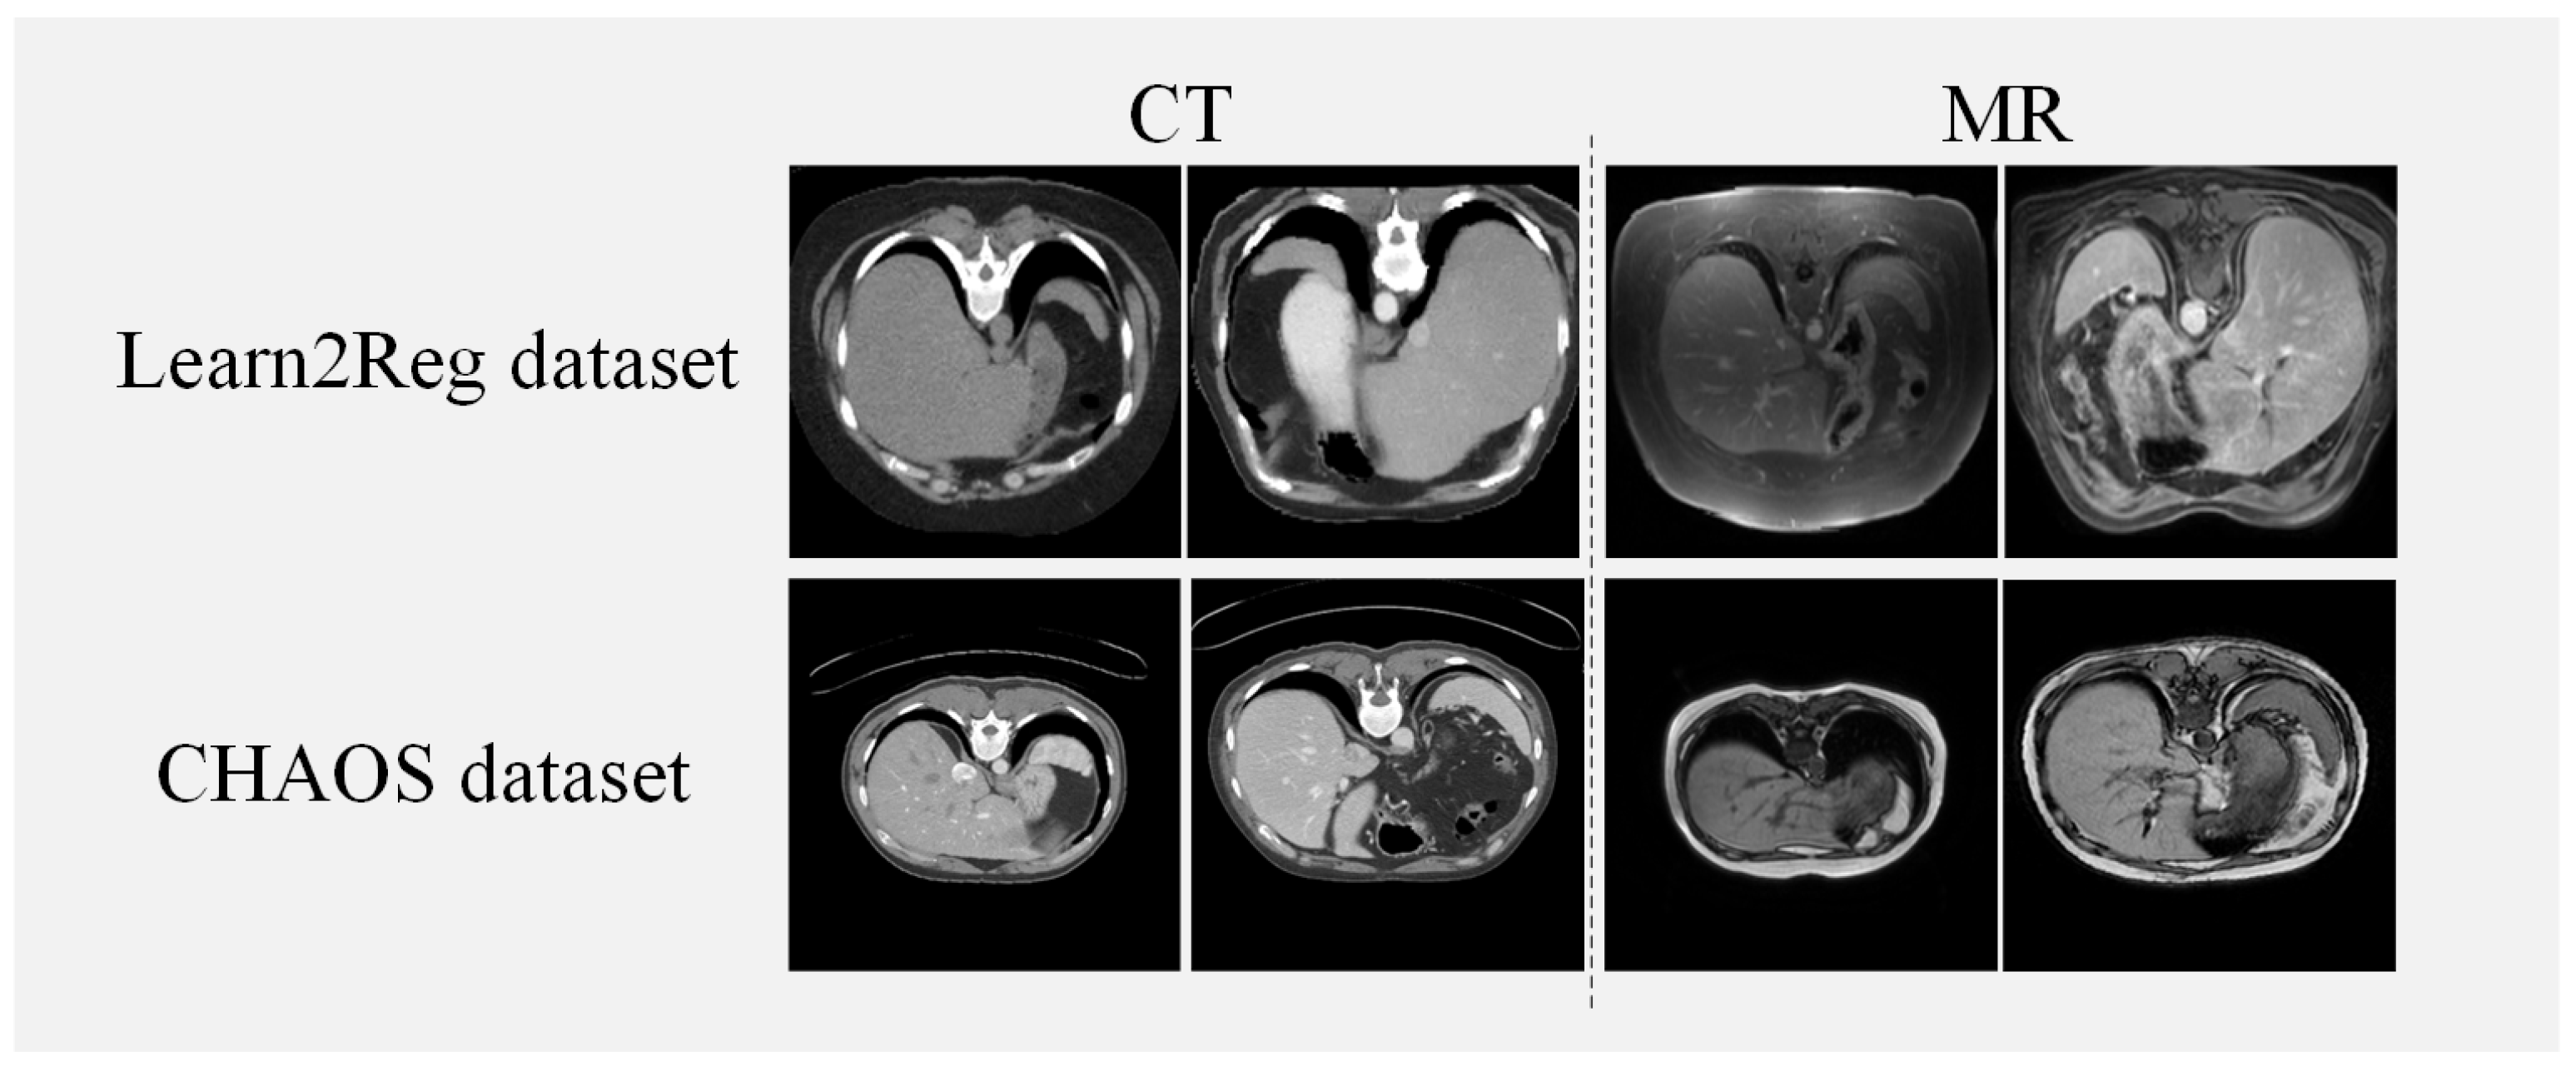

We utilize two abdominal datasets for verifying the effectiveness of our method, the Learn2Reg dataset [35] and the CHAOS dataset [36]. The Learn2Reg dataset consisted of 16 MRI and CT datasets and each scan included the liver, spleen, and left and right kidneys, four organs, which were labeled with manual and automatic organ segmentation. Each scan had a 3D volume of size 192 × 160 × 192 with a voxel spacing of 2 mm. For the experiment, we use Elastix [37] for coarse affine registration and set the train/validation/test datasets in 10/2/4 pairs randomly. The healthy abdominal organs were from 80 patients, where 40 of them went through CT scans and 40 of them went through MRI scans in the CHAOS dataset. We use 20 volumes of CT and T1-DUAL MRI images in the CHAOS dataset and randomly divide them into 14/2/4 pairs for train/validation/test datasets. For the preprocessing of both datasets, we select 70 central slices of each piece of data for our experiments. The input size of the slice is 256 × 256. Figure 4 illustrates examples from both the Learn2Reg dataset and the CHAOS dataset. Table 1 shows a concise description of the two datasets utilized in our method.

Figure 4.

Instances from the Learn2Reg and CHAOS datasets.